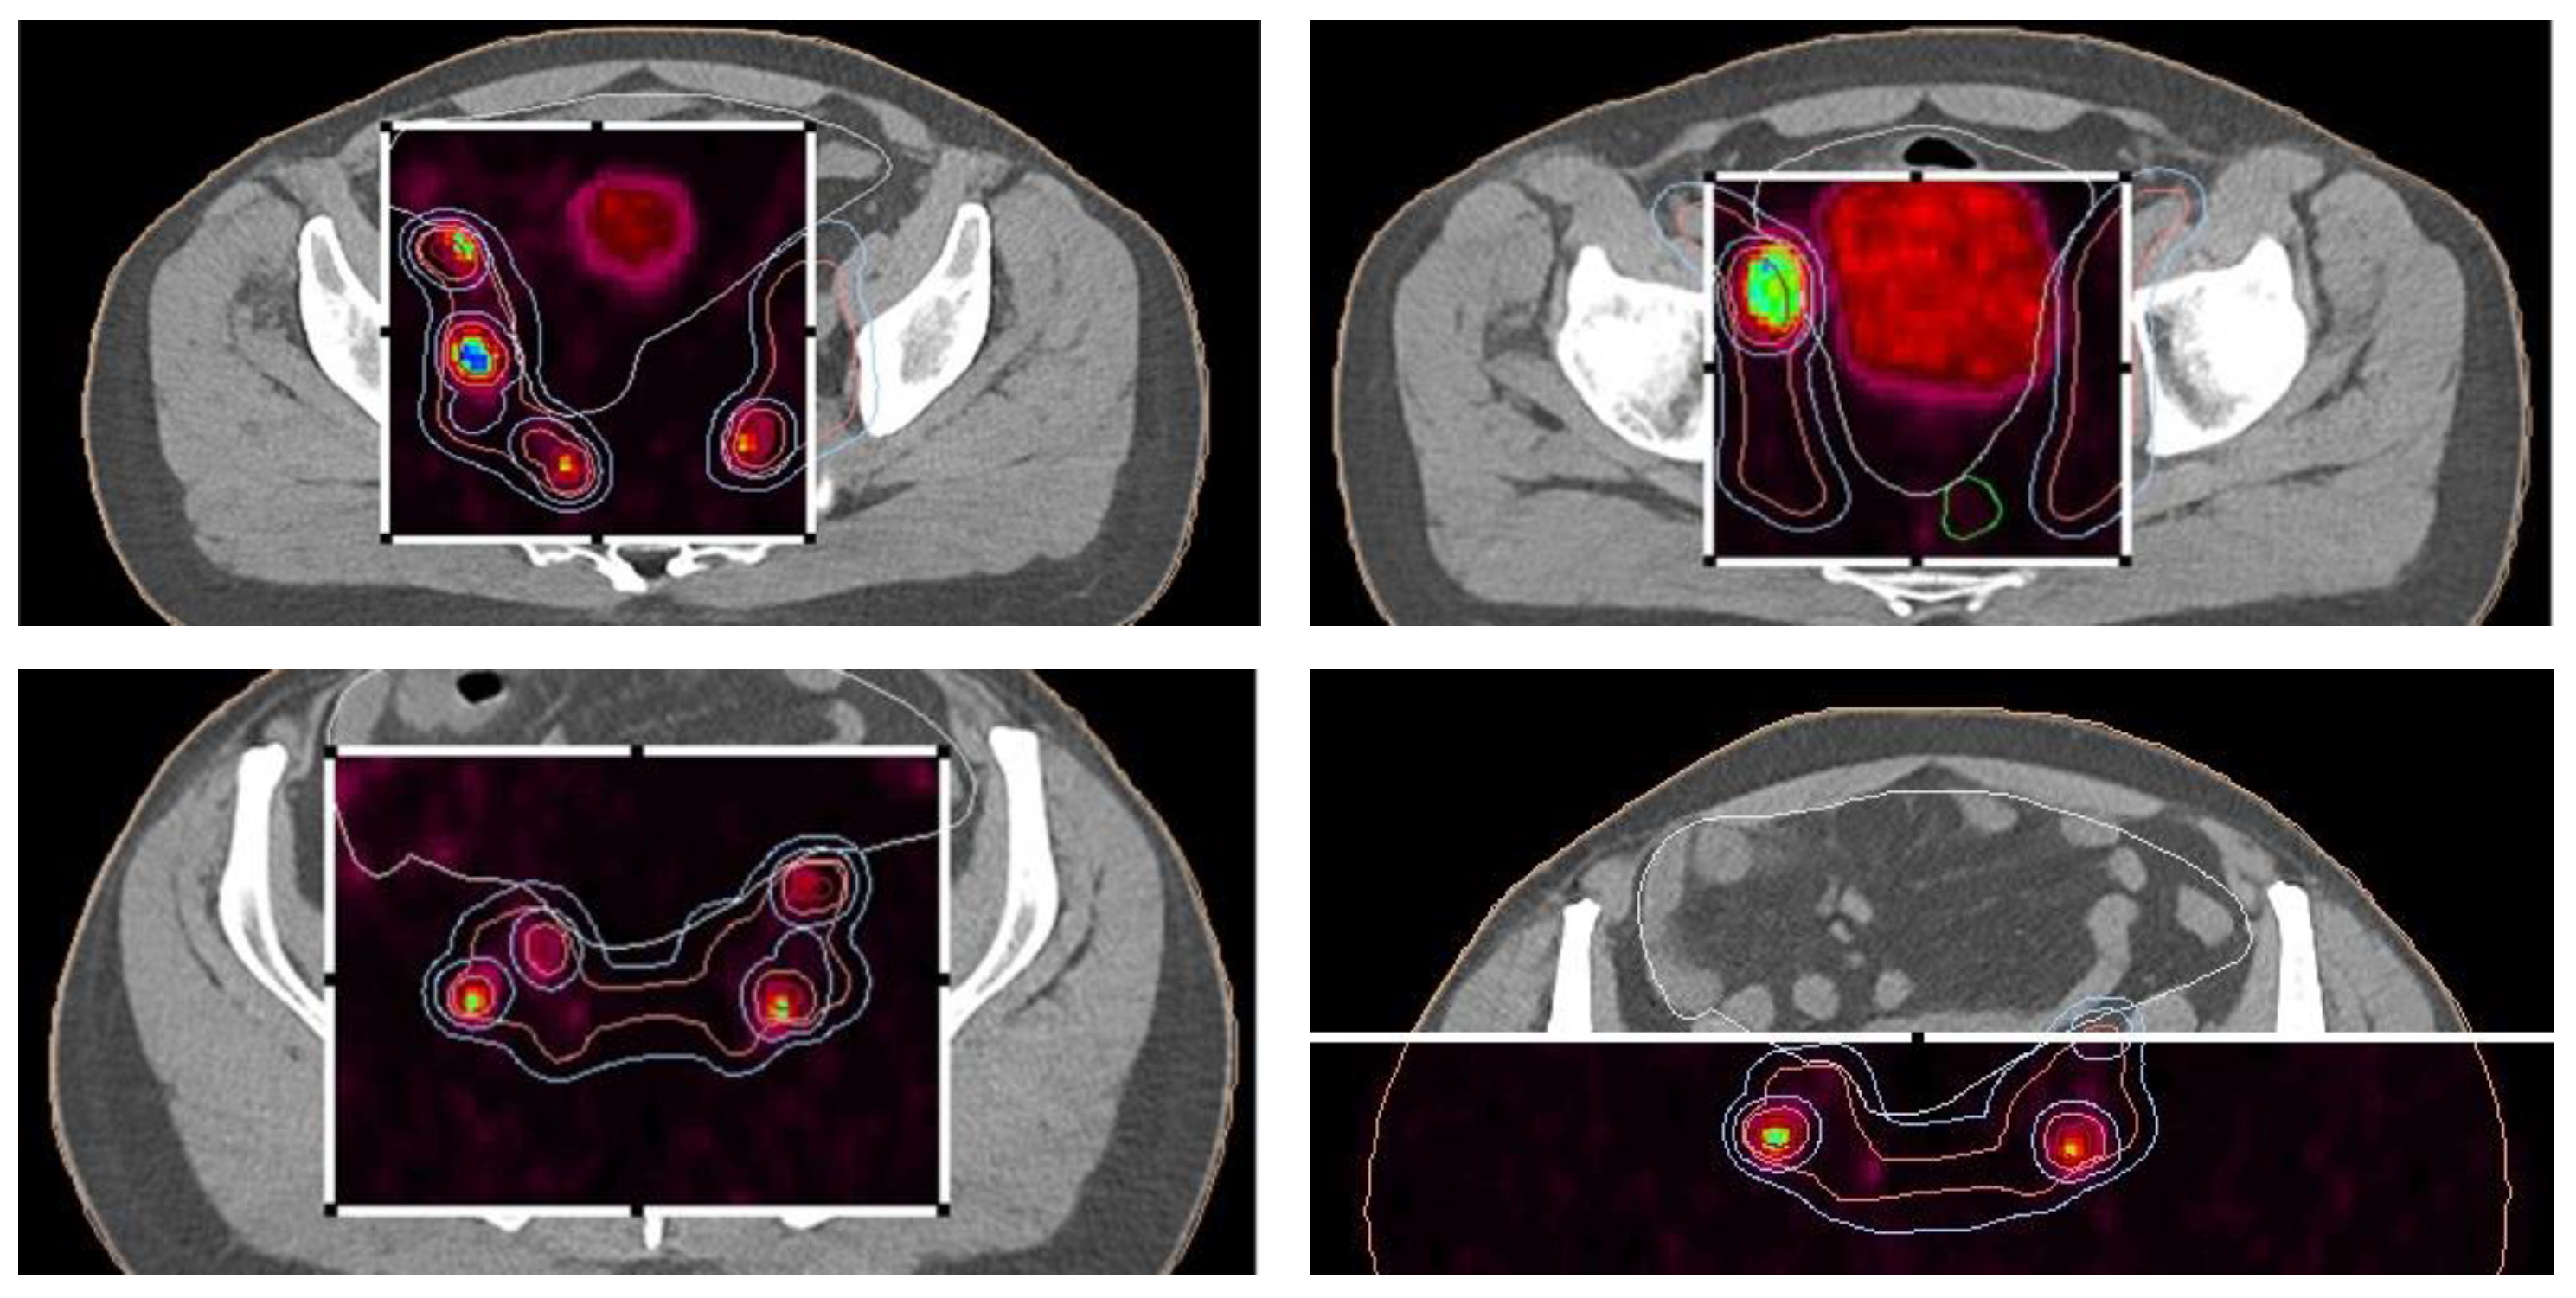

During the planning phase of the radiotherapy treatment course, a PET/CT scan was performed to delineate the metastatic sites accurately and guide radiotherapy planning. The radiotherapy regimen included teleradiotherapy targeting the prostate and affected lymph nodes with radical intent, utilizing a simultaneous integrated boost (SIB) approach with 45 Gy/60 Gy delivered in 25 fractions (Figure 2). Additionally, a high-dose–rate (HDR) brachytherapy boost of 15 Gy was administered in a single fraction to the prostate to achieve maximum local control (Figure 3).

Pre-radiotherapy PET-CT imaging (Figure 5) showed extensive lymph node metastases and high metabolic activity in the prostate. Following radiotherapy, the patient’s PSA level dropped below the edge of detection, indicating complete biochemical remission. This significant response was confirmed through follow-up imaging and clinical assessments.

Figure 5. Radiotherapy treatment planning—PET-CT—showing metastatic sites in the prostate and lymph nodes.